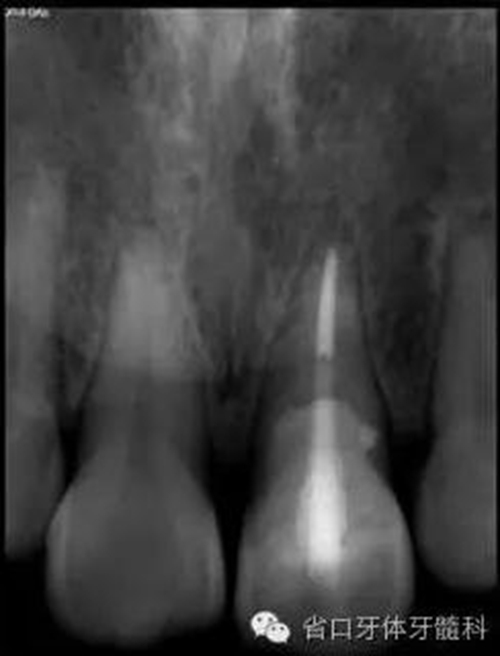

圖17. 術(shù)后X線片